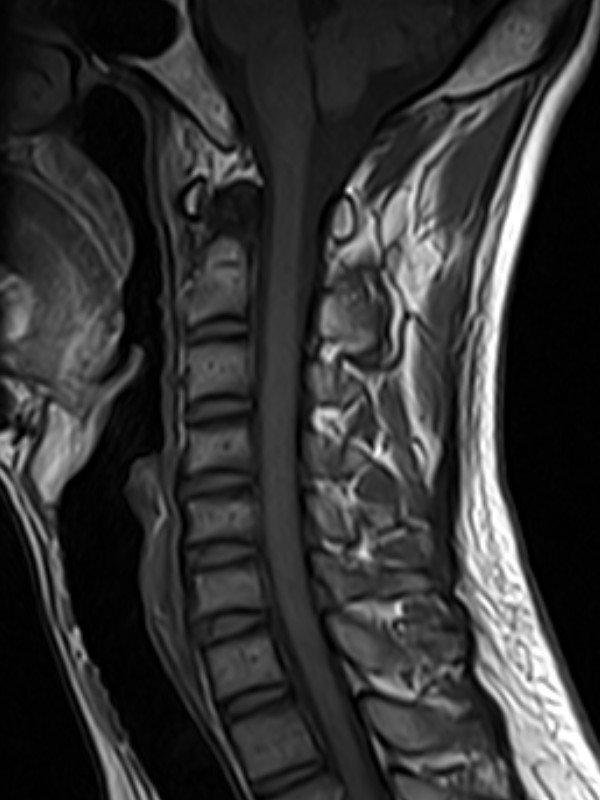

颈椎-T2